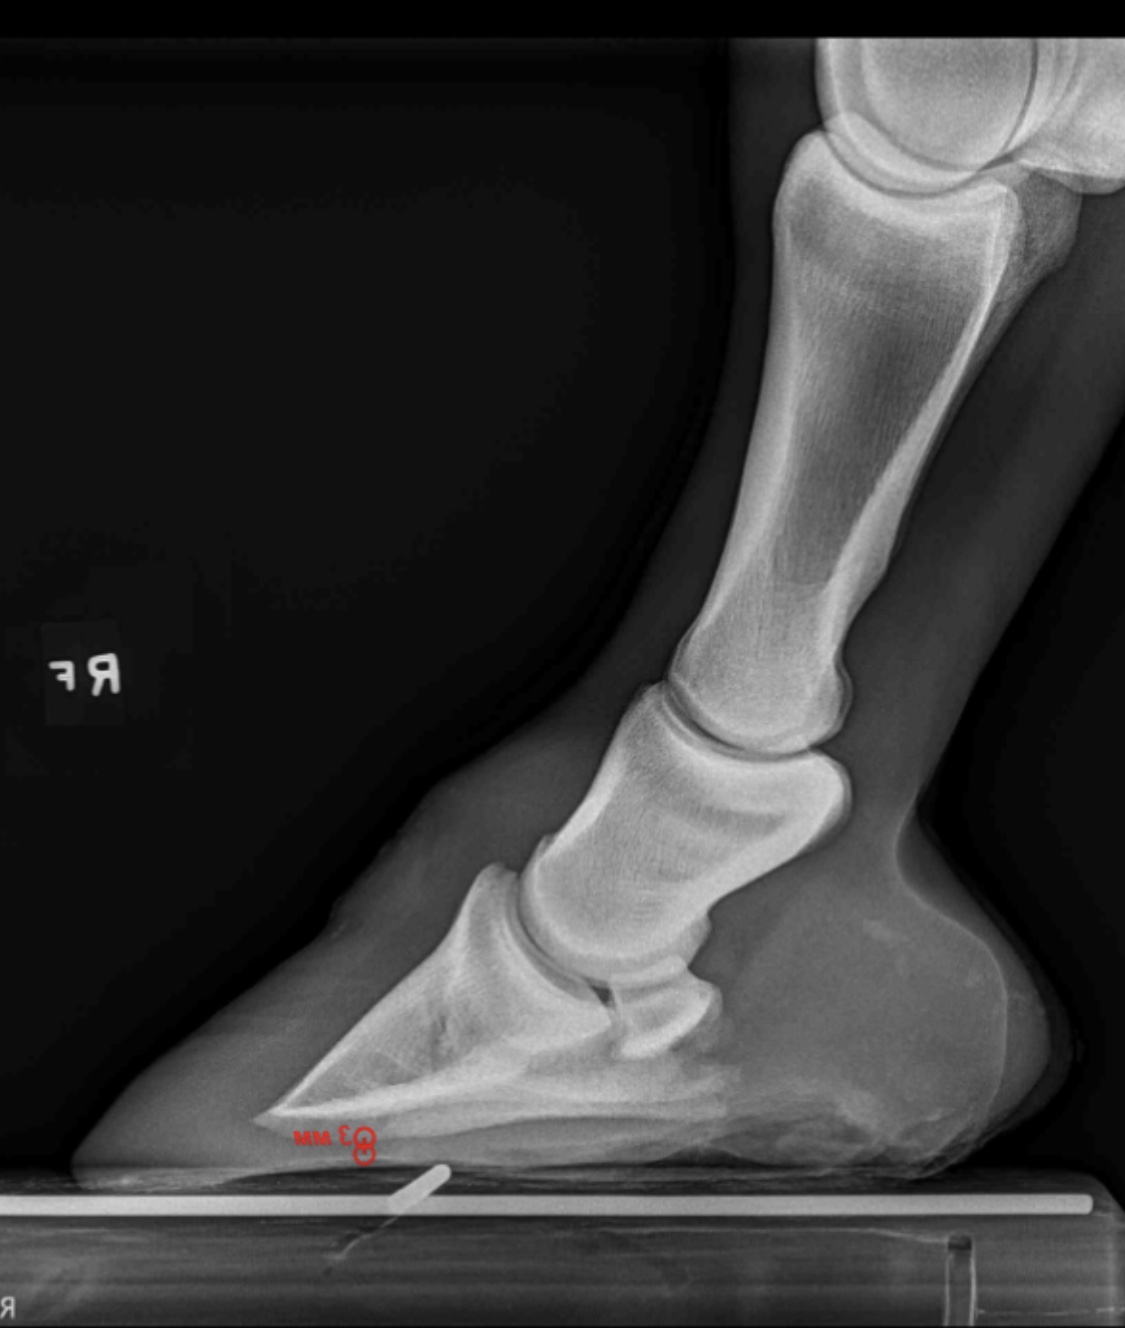

Pathologic fractures due to infection have a grave prognosis. The infection can involve the coffin bone, sole structure, laminae and the hoof wall. Chronic laminitis, excessive hoof length, flares, hoof cracks, and poor quality horn are all conditions that give the organism an opportunity to invade the hoof capsule and set up the infection.

This can be seen as an increased black filling or lack of density to the peripheral edge of the coffin bone, which indicates bone loss. Inflammation near the pedal or coffin bone; Horses with coffin bones weakened by any disease are also predisposed to this internal abscessing.

Create a free account with thehorse.com to. Upon arrival the horse suffered from severe coffin bone rotation located in the left front hoof capsule. The pressure from the infection and swelling of the soft tissues/laminae makes this condition very painful.

Palmar digital neurectomy is a very viable alternative once the bone has had time to heal. This type of infection is usually associated with abnormalities or defects in the hoof. With the weight of the horse pushing the coffin bone toward the ground and the pull of the deep digital flexor tendon rotating the coffin bone, the coffin bone will sink and rotate within the hoof.